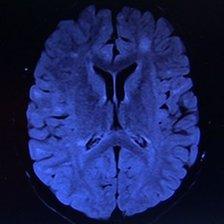

The lighter areas in this scan of Emily's brain shows where damage has occurred

At Birmingham Children's Hospital, I'm shown a scan of Emily's brain by Michael Absoud, a clinical research fellow at the University of Birmingham.

Dr Absoud points to lighter areas on the scan which are scars left on the brain after an attack of multiple sclerosis.